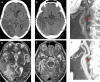

Carotid free-floating thrombus (FFT) is very rarely diagnosed in patients with acute ischemic stroke. It is a real clinical emergency due to the significant risk of death associated with thromboembolic complications. Herein, we present three patients with ischemic stroke caused by carotid FFT after less than 20 days from administration of mRNA vaccine BNT162b1 (Pfizer/BioNTech) for Severe Acute Respiratory Syndrome-CoronaVirus 2 (SARS-CoV-2). To our knowledge, these are the first cases reporting carotid FTT following SARS-CoV-2 vaccination.